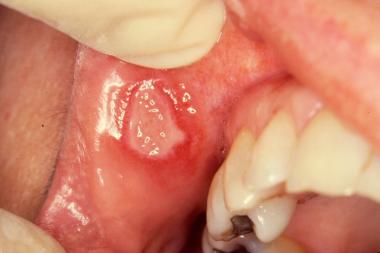

Áp tơ khổng lồ

- Dạng lâm sàng nặng nhất (10%).

- Vị trí: khẩu cái mềm, trụ amidan, môi, lưỡi.

- Triệu chứng bệnh: Nhiều vết loét sâu (5-10), 1-3cm, viền viêm đỏ rất đau.

- Thời gian lành thường: 2-6 tuần (có sẹo).

- Tái phát liên tục.

- Sức khoẻ toàn thân bị ảnh hưởng.